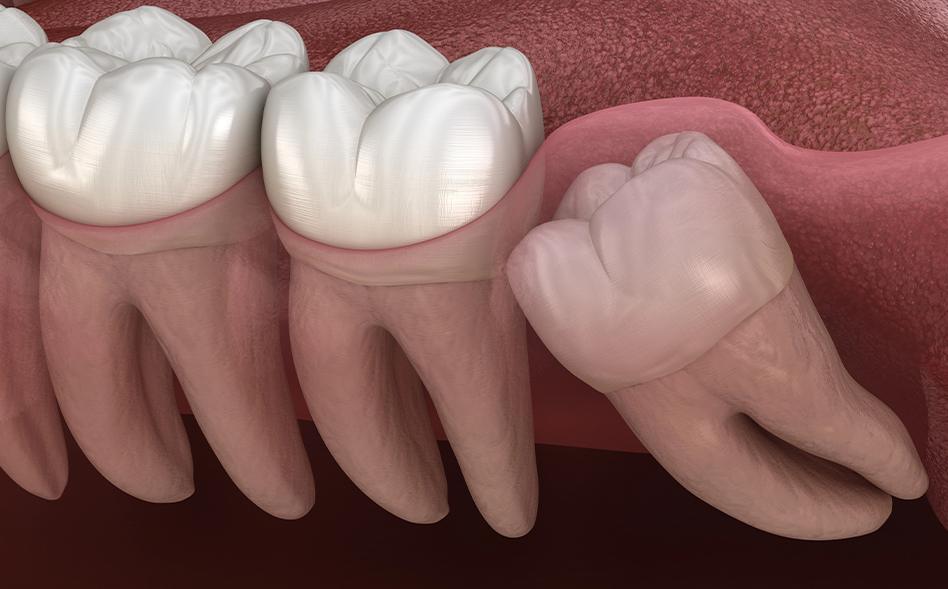

Wisdom tooth extraction is often a proactive step to prevent infection, misalignment, or long-term oral health complications. By addressing concerns promptly, we can help you avoid more complex treatment later while protecting both your health and your smile.